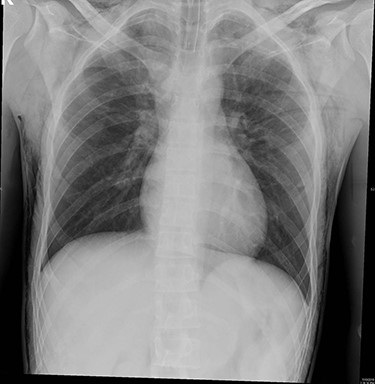

The patient was kept under observation for 24 hours. ABG was performed revealing the following values: pH 7.44; PaCO2 35.9 mmHg; HCO3 24.1 mmol/l and PaO2 90.8 mmHg. The final pre-discharge radiography showed improvement in the SE (Fig. 2) which has been resolved spontaneously.

Final pre-discharged x-ray showed improvement of the SE compared to the intra-operative x-ray.